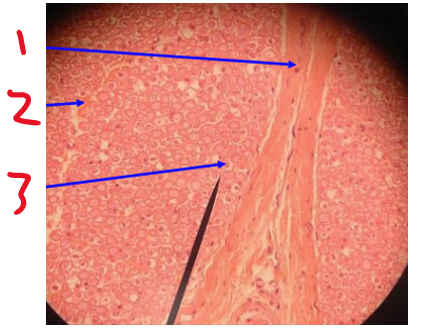

Name 1

perineurium

Name 2

endoneurium

Name the dot at 3

axon

Name the white surrounding the dot at 3

myelin sheath